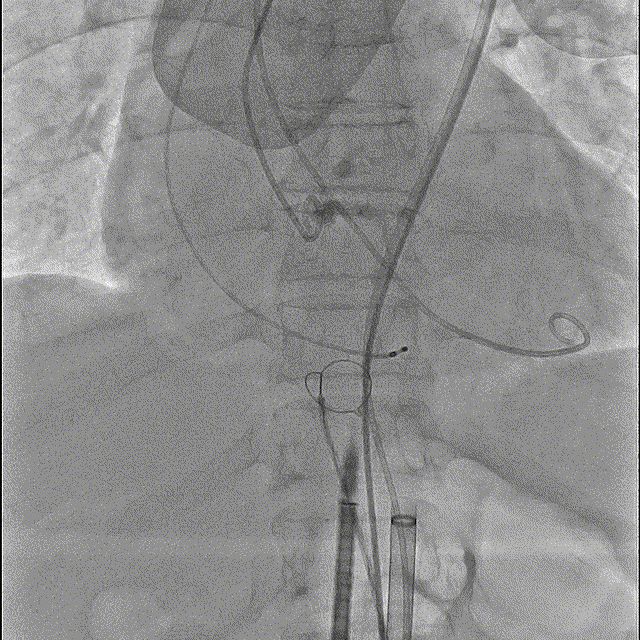

15点30,杂交手术室刚结束上台手术,患者随即进入导管室,此时患者血压为93/50mmHq、心率94次/分。病情紧急,麻醉科陈玉培教授凭借过硬功底,快速完成桡动脉穿刺测压、深静脉置管、诱导麻醉及气管插管;超声科朱叶锋先用经胸超声进行细致检查;导管室张长志护士长带领护士彭丽娟,技师杨杰同时完成了监护、导尿、仪器术前准备;介入医师进行消毒、器械准备以及瓣膜装配;ECMO小组也已经完成准备工作。

手术过程

猪尾中部初始定位

初始释放定位